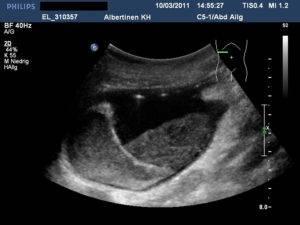

УЗИ желчного пузыря

Норма наблюдается при показателях, когда орган обладает:

- Грушевидной и цилиндрической формой.

- Шириной от трех до пяти сантиметров.

- Длиной от шести до десяти сантиметров.

- Объемом от тридцати до семидесяти кубических сантиметров.

- Толщиной стенок не больше четырех миллиметров.

- Объемом общего канала от шести до восьми миллиметров.

- Поперечными долевыми протоками не больше трех миллиметров.

- Четкими очертаниями.

Если у пациента норма в показателях отсутствует, то принято говорить о развитии аномального процесса в органе.

При холецистите острого характера толщина стенок остается в норме, но сам желчный пузырь имеет большие размеры. При этом внутри располагаются перегородки, что ведет к усилению кровообращения в желчном пузыре.

При холецистите хронической формы желчный пузырь, наоборот, имеет меньшие размеры. Но толщина стенок гораздо больше. При этом наблюдается их уплотнение и деформирование. Из-за этого орган имеет нечеткий контур с небольшими просветами.

Если у пациента наблюдается дискинезия органа, то при ультразвуковом диагностировании видно, что желчный пузырь имеет перегиб. Ко всему этому, стенки сильно утолщены и наблюдается повышенный тонус.

Если у больного возникла желчнокаменная болезнь, то в полости органа проявляются образования. При этом наблюдается утолщенность стенок органа и нечеткое очертание.

При разрастании полипов на стенках желчного пузыря можно заменить образования округлой формы. Если полип имеет размер меньше одного сантиметра и при этом он не растет, то он имеет доброкачественный характер и не повлияет на общее состояние больного. Если образование имеет размер больше одного сантиметра, при этом наблюдается его рост, то это злокачественная опухоль, которая ведет к деформированию желчного пузыря.

Полип в желчном пузыре